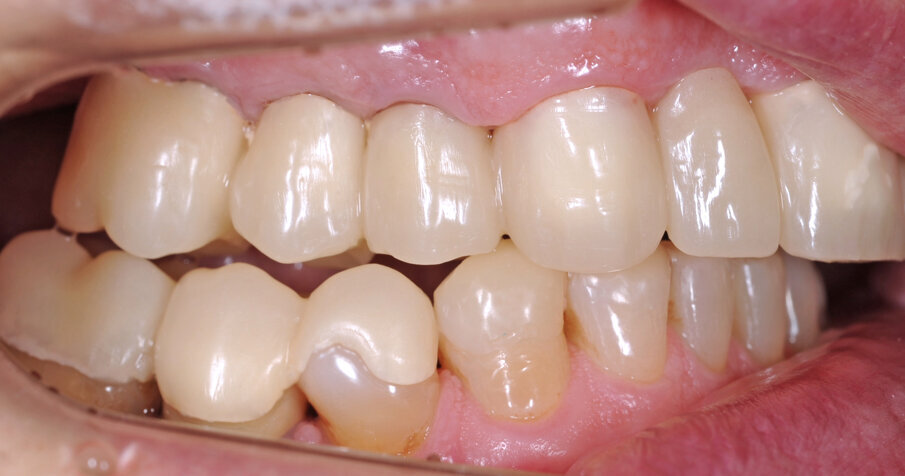

Il fresato ottenuto è poi riportato su articolatore Reference SL – già opportunamente programmato – e viene dall’Odontotecnico competente più precisamente funzionalizzato secondo i criteri della programmazione funzionale sequenziale, evidenziando con cere colorate i rapporti di centrica, le funzioni di mediotrusiva e protrusiva e le protezioni retrusive. I monconi sfilabili consentono la modellazione della sequenzialità mediotrusiva con la guida incisale indicata dalla registrazione axiografica (blu) (Figg. 34-37). La ceratura sequenziale è ora scansita con Sirona InEos X5 su Exocad, ed il modellato viene ricontrollato al CAD per spessori, connessioni e morfologia, e nella regolazione degli offsets per la ripreparazione dei monconi, ed è inviato al CAM per la fresatura dei II provvisori in Bredent breCAM.multicom, un PMMA con microriempitivo ceramico ad alta stabilità, su Dental Plus 5 Axis Milling Machine. La rifinitura dei monconi è seguita da ribasatura dei II provvisori in TRP - previo isolamento di tutte le superfici funzionali - e gli stessi sono poi rifiniti e lucidati. I soli elementi 3.3, 4.2 e 4.3 sono rimodellati in regione incisale con addictions in composito, secondo la morfologia studiata in ceratura. La consegna conferma la buona integrazione dei manufatti dal punto di vista estetico, occlusale, articolare e neuromuscolare, con controllo occlusale conforme al progetto (Figg. 38-42).

Il paziente utilizza questi secondi provvisori per otto settimane, durante le quali conferma la buona integrazione dei restauri e la soddisfacente funzione occlusale. Ciò è verificato con l’esecuzione di una nuova axiografia elettronica che già a due settimane dalla consegna evidenzia una buona risposta muscolare al nuovo design occlusale ed alla nuova postura mandibolare in TRP (Figg. 43-46). Provvediamo infine alle impronte per la costruzione dei manufatti definitivi in Zirconia-ceramica. I modelli sono scansiti in laboratorio con inEos X5 (Dentsply Sirona) su exocad (Figg. 47-49), ed una seconda scansione viene eseguita con i provvisori del Paziente posizionati sui modelli (Figg. 50-52). Il CAD consente di eseguire un matching fra le due scansioni, per cui i secondi provvisori utilizzati in TRP, con funzione occlusale sequenziale già completamente programmata, sono utilizzati per definire le morfologie dentali definitive di tutti gli elementi da restaurare (Figg. 53, 54) secondo il rapporto intermascellare definito (Figg. 55-58). Si esegue quindi fresatura al CAM della protesi definitiva in zirconia (Figg. 59, 60), la stratificazione e finitura ed infine la consegna al Paziente con cementazione in Panavia V5 (Figg. 61-65).